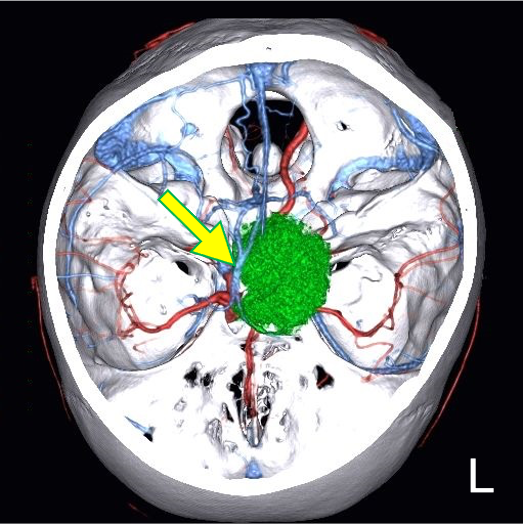

図7.造影後T1WI、4D-CTAngiographyのFusion像

thalamostriate vein, internal cerebral vein(矢印)を圧排する病変(緑)を認める。

1. 本症例は神経膠腫や悪性リンパ腫などとの鑑別も必要となる実質内腫瘍であるが、診断を進めるうえで、病変の形態や内部性状の把握のための検査として、造影MRIの役割がある。

2. 生検実施に際して使用するニューロナビゲーターのデータとして、精細な造影MRIは必要かつ有用である。術前検討のFusion 像においても、造影される病変と血管の位置関係の把握が可能であった。脳深部の病変へ確実に到達するために、手術支援の見地から造影MRIは有用な検査である。